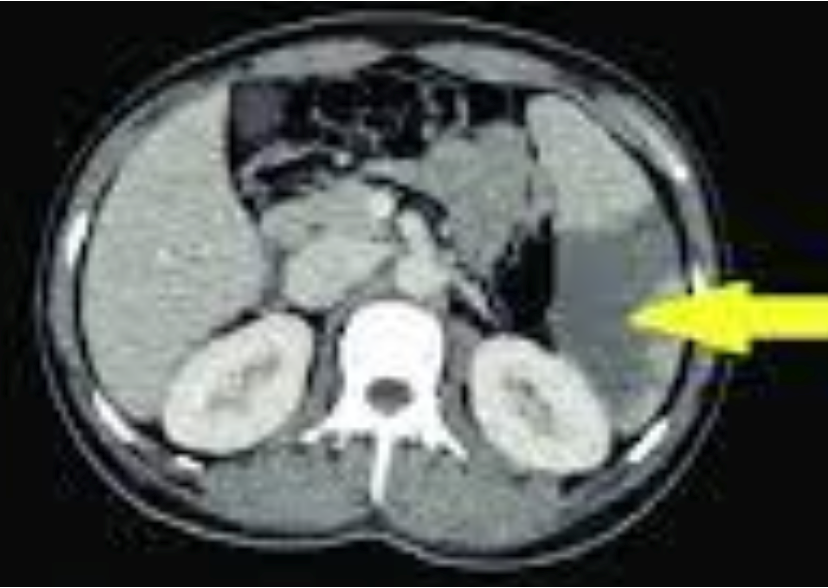

- Infarction spleen: arterial embolism,

- Asymptomatic/ pain LUQ.

- CT: hypo-perfused area